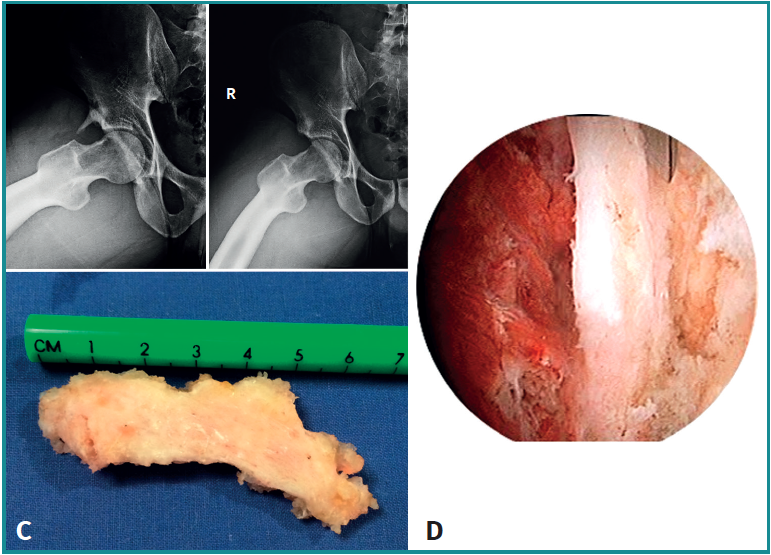

- Características y morfología radiográfica: en estos casos se visualizará la calcificación cerca del borde superior del acetábulo, generalmente paralela al eje longitudinal del fémur y con 3 posibles variantes: filiforme corto (tipo B1), filiforme largo (tipo B2) y redondeado o difuso (tipo B3)(3)(Figura 6). En los tipos filiformes el aspecto de cola de cometa es característico. Es importante tener en cuenta que existen otras causas de mineralización relacionadas con la porción directa del recto anterior proximal, como las avulsiones de la espina ilíaca anteroinferior o los diferentes tipos de pinzamiento de tipo subespinal.

- Localización y lesiones asociadas: adyacente al borde superior del acetábulo y con deformidades de tipo cam o pincer asociadas en muchos casos.

- Tratamiento: aunque la mayoría de los casos de tendinitis calcificante del recto anterior son autolimitados, los pacientes con molestias moderadas a graves pueden beneficiarse de las opciones de tratamiento no quirúrgico, como el barbotaje guiado por ecografía o TAC o el lavado y la inyección de esteroides. En casos de persistencia de síntomas o la existencia de una calcificación grande, debe ser considerada la extirpación quirúrgica. Las recientes mejoras en la artroscopia de cadera permiten tratar esta patología de una manera menos invasiva que la clásica cirugía abierta por vía anterior, con la ventaja adicional de abordar los trastornos concomitantes intra- y extraarticulares, como el pinzamiento femoroacetabular o subespinal(7,8,9)(Figura 7). Tras la cirugía se debe considerar tratamiento con antiinflamatorios no esteroideos durante 3-6 semanas con el fin de evitar calcificaciones regionales(10).